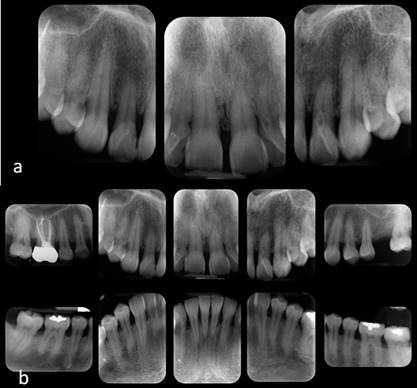

Paciente femenino de 38 años de edad, ASA I, aparentemente sana, sin antecedentes personales de relevancia y hábito de tabaquismo y toxicomanías negado, llegó en mayo del 2016 a la clínica de prótesis de la Escuela Nacional de Estudios Superiores unidad León de la UNAM con motivo de consulta “quiero arreglarme los dientes de adelante”. La paciente fue valorada protésicamente y se remitió al área de periodoncia para valoración periodontal, donde se obtuvo como diagnóstico periodontitis crónica generalizada moderada. Después de pasar por la fase I periodontal (eliminación de cálculo, así como raspado y alisado radicular) y de tener a la paciente en fase de mantenimiento (Figura 1), se valoró para alargamiento de corona estético que abarcara del segundo premolar superior derecho al segundo premolar superior izquierdo (15-25) para posterior rehabilitación protésica. Radiográficamente se observó una porción corona-raíz y altura adecuada de hueso alveolar (Figura 2a y 2b). A la inspección clínica se observó diastema en los centrales superiores, pérdida de papilas, discrepancia de los márgenes gingivales en la zona anterosuperior y un biotipo gingival grueso (Figura 3a), al igual que una línea de sonrisa alta (Figura 3b). Según las condiciones de la paciente y las consideraciones para realizar un alargamiento de corona, se decidió que el procedimiento era viable. El área de prótesis realizó la guía quirúrgica (mock up) según el encerado diagnóstico y análisis de sonrisa digital diseñado.